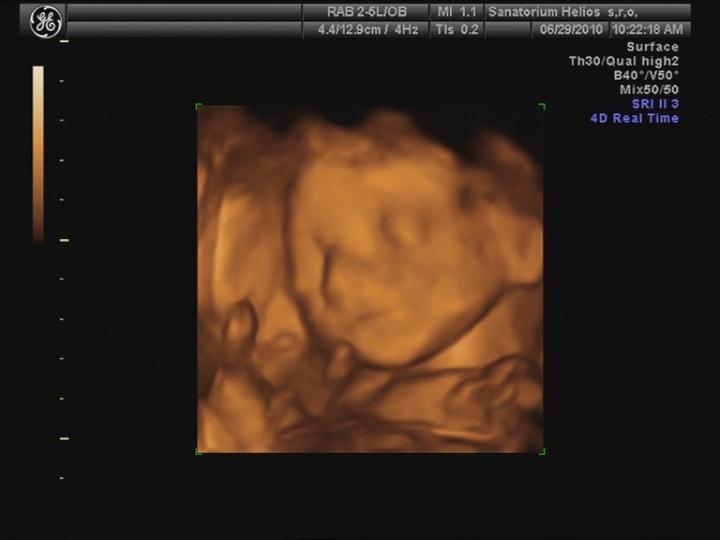

Byla jsem na UTZ, odpovídáme 10+4 tt a všechno je v pořádku... 🙂